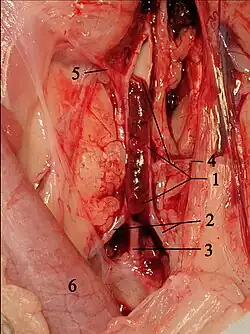

Bei Katzen entstehen die Blutgerinnsel vor allem im linken Herzohr.[9] Sie oder Teile von ihnen werden mit dem Blutstrom mitgerissen, gelangen über die linke Herzkammer in die Aorta, bleiben an Gefäßabgängen hängen und verstopfen diese. Dieser Zustand wird als Thromboembolie oder Thrombembolie bezeichnet. Bei Katzen tritt dies überwiegend in der Aorta im Bereich ihrer Endaufzweigung, also am Abgang der beiden äußeren Beckenarterien (Aa. iliacae externae), auf. Dies wird auch als „Sattelthrombus“ oder als „Reitender Thrombus“ bezeichnet. Dadurch kommt es zu einer Blutunterversorgung der hinteren Extremitäten. Zusätzlich werden durch die Blutplättchen Thromboxan und Serotonin freigesetzt, welches zu einer Gefäßverengung und damit zu einer Minderdurchblutung auch nicht direkt betroffener Blutgefäße führt. Serotonin stimuliert darüber hinaus Schmerzfasern, was zu der hohen Schmerzhaftigkeit der Erkrankung beiträgt.[10] Nur in 10 % der Fälle sind andere Blutgefäße betroffen, beispielsweise die Oberarmarterie, die Lungenarterien, Hirngefäße, Darmgefäße oder Herzkranzgefäße.[11][12]

Die naheliegende Behandlung, die Wiedereröffnung des Gefäßes durch medikamentöse Auflösung (Thrombolyse) oder invasive Entfernung des Gerinnsels (Thrombektomie), wie sie in der Humanmedizin bei Verschlusskrankheiten wie Schlaganfall oder Herzinfarkt lange etabliert ist, liefert bei Katzen unbefriedigende Ergebnisse und wird daher nicht mehr empfohlen.[33] Die Thrombolyse mit Streptokinase, Urokinase oder Gewebespezifischem Plasminogenaktivator hat in verschiedenen Studien keine Verbesserung des Behandlungserfolgs erbracht. Hierbei kommt es meist zu häufig tödlich verlaufenden Reperfusionstörungen, Hyperkaliämie, metabolischer Azidose, Nierenversagen und Blutungen, so dass die Überlebensrate häufig geringer ist als mit konservativer Behandlung.[47][48] Solche Behandlungen werden in der Humanmedizin nur in hochspezialisierten Einrichtungen (Herzzentren, Stroke Units) mit hohem personellen und apparativen Aufwand durchgeführt. In der neueren Literatur gibt es jedoch Hinweise, dass Alteplase und Reteplase die Rekanalisation fördern.[4] Die chirurgische Beseitigung des Thrombus wird in der Tiermedizin aufgrund der damit verbundenen Risiken ebenfalls selten durchgeführt, obwohl sie in Einzelfällen erfolgreich sein kann.[49] Sie ist mit den gleichen Komplikationen vergesellschaftet wie die Thrombolyse und wird deshalb nicht mehr empfohlen. Daher wird gegenwärtig auf die körpereigene Auflösung des Gerinnsels und damit auf die spontane Rekanalisation gesetzt, die in knapp 40 % der Fälle schnell genug eintritt.[47]